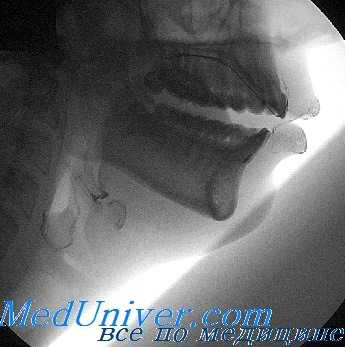

а) На рисунке представлено короткое мягкое нёбо, которое во время сокращения поднимающих его мышц в целях разъединения носоглотки и ротоглотки, своим свободным краем касается слизистой оболочки глотки в области её свода, а не задней стенки, как это имеет место в норме. В формировании голоса главную роль играет не столько длина мягкого нёба, сколько его подвижность.